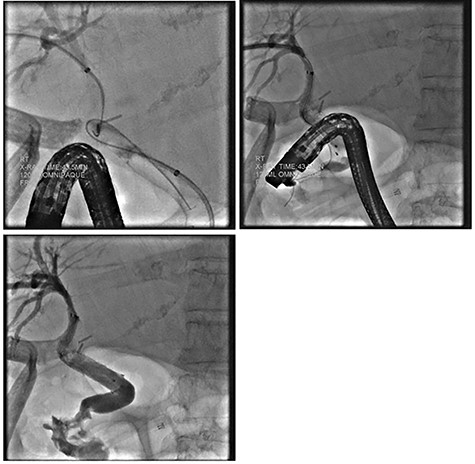

Intraoperatively, a distended, friable, gangrenous gallbladder was encountered, requiring conversion to open procedure. A Strasburg Type D partial laceration to the common bile duct (CBD) was confirmed with intraoperative cholangiogram and repaired primarily over a T-tube. A Jackson-Pratt (JP) drain was placed near the repair (Fig. 1).

Intraoperative cholangiogram demonstrating Strasburg Type D BDI [1].